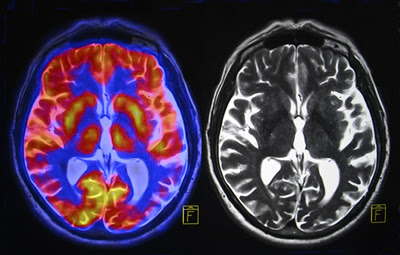

๐—›๐—ผ๐˜„ ๐Ÿฑ-๐— ๐—ฒ๐—ข-๐——๐— ๐—ง ๐—ฎ๐—ณ๐—ณ๐—ฒ๐—ฐ๐˜๐˜€ ๐˜๐—ต๐—ฒ ๐—ฏ๐—ฟ๐—ฎ๐—ถ๐—ป.

And the crazy part is, it doesnโ€™t work like ANY other psychedelic ever studied.

It might be closer to a ๐˜ค๐˜ฐ๐˜ฎ๐˜ข than a trip ๐Ÿงต Image

Hereโ€™s what makes this study different.

Normally, psychedelic studies ask:

โ€œ๐˜๐˜ฐ๐˜ธ ๐˜ด๐˜ต๐˜ณ๐˜ฐ๐˜ฏ๐˜จ ๐˜ข๐˜ณ๐˜ฆ ๐˜ต๐˜ฉ๐˜ฆ ๐˜ฃ๐˜ณ๐˜ข๐˜ช๐˜ฏ๐˜ธ๐˜ข๐˜ท๐˜ฆ๐˜ด?โ€

โ€œ๐˜๐˜ฐ๐˜ธ ๐˜ฎ๐˜ถ๐˜ค๐˜ฉ ๐˜ข๐˜ญ๐˜ฑ๐˜ฉ๐˜ข ๐˜ฅ๐˜ณ๐˜ฐ๐˜ฑ๐˜ฑ๐˜ฆ๐˜ฅ?โ€

โ€œ๐˜๐˜ฐ๐˜ธ ๐˜ฎ๐˜ถ๐˜ค๐˜ฉ ๐˜ฅ๐˜ฆ๐˜ญ๐˜ต๐˜ข ๐˜ช๐˜ฏ๐˜ค๐˜ณ๐˜ฆ๐˜ข๐˜ด๐˜ฆ๐˜ฅ?โ€

That tells you ๐—ถ๐—ป๐˜๐—ฒ๐—ป๐˜€๐—ถ๐˜๐˜†.

This team asked a better question.Image

โ€œHow does information actually ๐—บ๐—ผ๐˜ƒ๐—ฒ through the conscious brain?โ€

So instead of just measuring wave strength, they mapped:

โ€ข Where signals start

โ€ข Where they travel

โ€ข Whether patterns repeat

โ€ข Whether the brain maintains a stable global structure

Something that had never been done on 5-MeO-DMT in humans before.Image